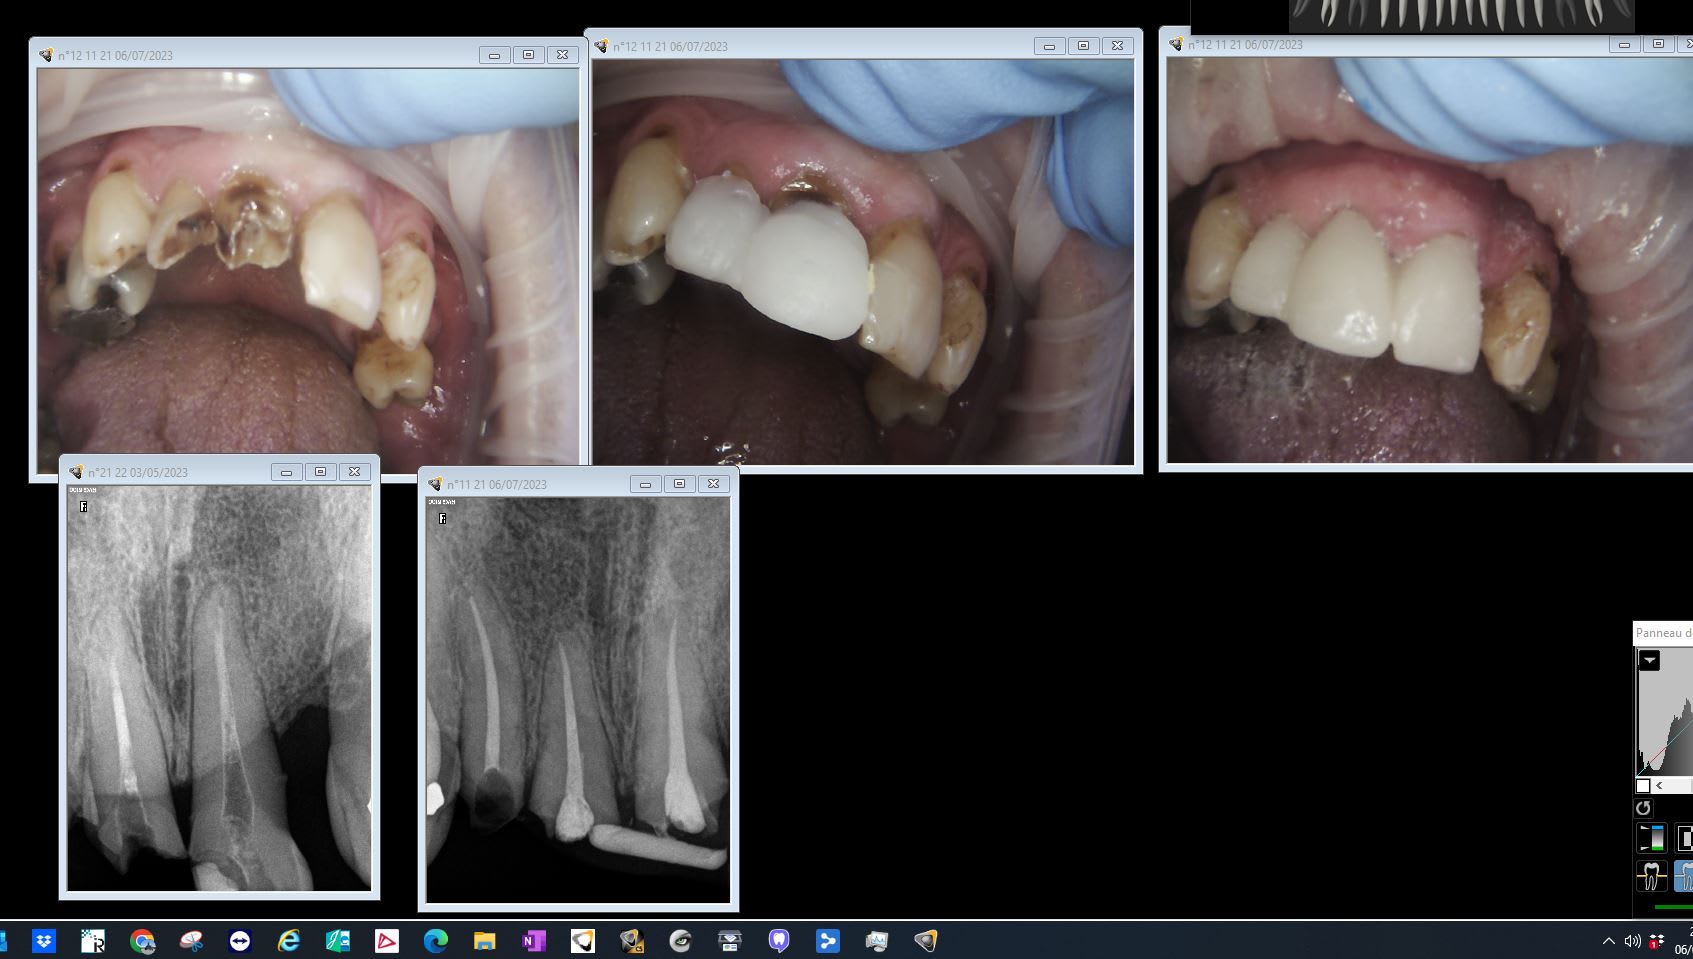

Dans le taille crayon sur bouches pourries. Comme ça tu culpabilises moins de ne pas être économe en tissus. C'est une source inépuisable en France. Notez le moke up au compo périmé. -)